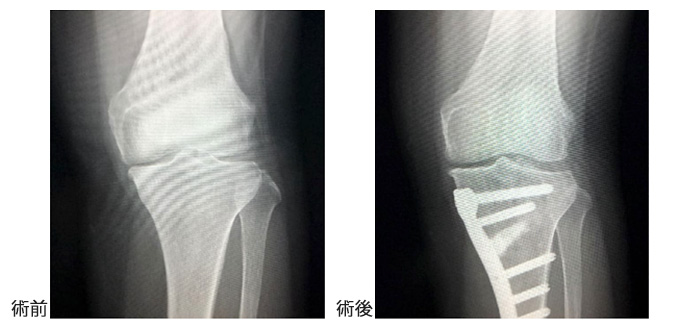

膝関節疾患の治療の基本は保存加療ですが、保存加療による効果がないと判断した場合は手術加療を行っています。変形性膝関節症や骨壊死に対しては、人工膝関節置換術・人工膝関節単顆置換術と高位脛骨骨切り術を症例に合わせて使い分けたり、患者さんの年齢・既往歴にもよりますが両側同時の手術も行っています。人工膝関節置換術においては、テンサーを用いた術中計測を正確に行うことによって、1mm・1度も狂いが生じないような手術を行っております。

高位脛骨骨切り術はO脚の方の脛骨(すねの骨)を内側から切り広げてX脚にするという手術です。広げた隙間には人工骨を挿入しますが、これらは数年でご自身の骨に置換されます。